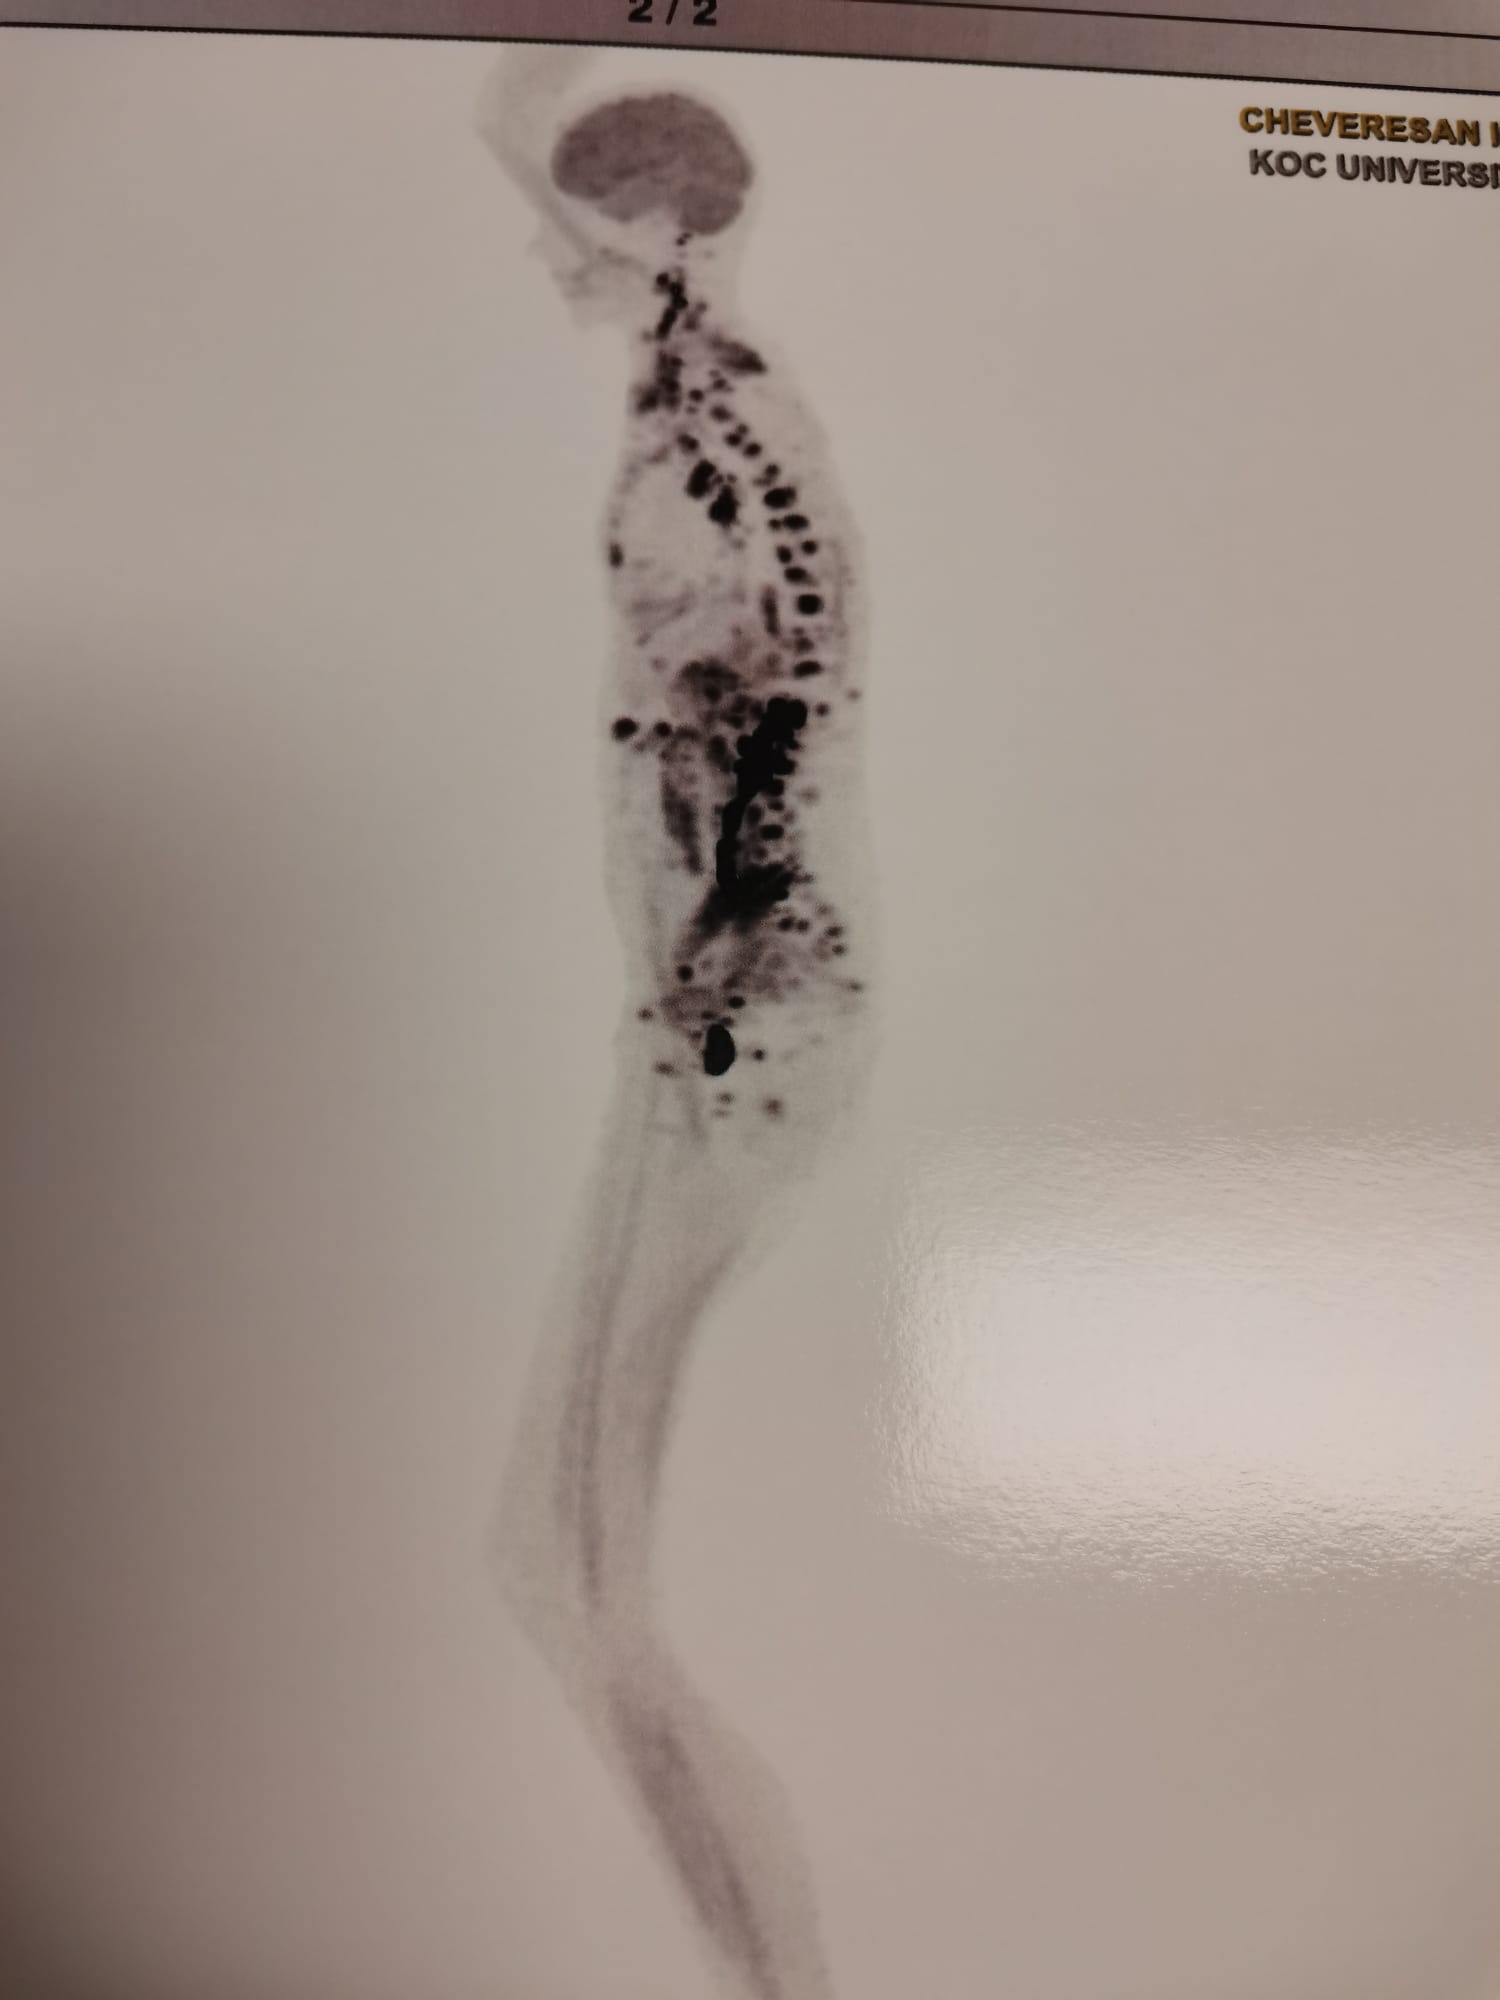

Pe Ionela nu o cunosc, dar îmi place să cred că e tot ce am scris mai sus și mult mai mult de atât. Nici voi nu o cunoașteți, dar niciodată nu v-ați făcut un scenariu în minte despre o persoană pe care nu o cunoașteți? Eu așa mi-o închipui pe Ionela. Ionela există – nu e în închipuirea mea – și suferă de o boală cumplită.Ionela avea părul blond și lung și o strălucire în ochi. Acum, Ionela nu mai are păr pe cap, iar ochii și-au pierdut din strălucire. Ionela era o zâmbăreață. Acum boala, chimioterapia, gândul că ar putea dipărea sunt imprimate, toate, pe chipul ei.Ionela are 30 de ani, locuia în Arad și era angajată la o societate comercială. Din luna iunie a acestui an, Ionela “locuiește” prin spitale. În 17 iulie, Ionela trebuia să facă nunta, să se căsătorească…Ionela dansa în ansamblul folcloric de la Dieci. Acum, este țintuită pe un pat de spital, în Turcia, iar corpul îi este „invadat” de metastaze. O săptămână de tratament, la spitalul din Turcia, unde este internată de la sfârșitul lunii octombrie, costă 13.000 de euro. Ionela trebuie să plătească în fiecare săptămână 13.000 de euro pentru a trăi. Medicii de aici i-au dat o speranță la viață, după ce cei din Austria – care i-au administrat tratament împotriva cancerului ovarian – au renunțat și i-au spus că singurul lucru pe care îl mai pot face pentru ea este un tratament paleativ. Prietenii Ionelei nu au renunțat când au auzit veștile. Au căutat și au căutat, peste tot, un spital, specialiști. Și au găsit. În Turcia.După tratamentul costisitor primit în Austria, din luna iunie și până în octombrie, Ionela a rămas fără bani. Prietenii ei au rămas fără bani. Donațiile au fost cheltuite pe tratament.Ionelei i s-a dat o șansă. Medicii de la spitalul din Turcia – unde este internată – i-au spus că are nevoie de 3-4 luni de chimioterapie și radioterapie, pentru a elimina/reduce din metastaze. Când se va întâmpla acest lucru, medicii o vor putea opera pe Ionela, vor putea scoate restul tumorilor din corpul ei și Ionela s-ar putea vindeca. Ionela ar putea trăi.Medicii din Turcia au stabilit, în fapt, după numeroase ore de investigații, că, în cazul bolii Ionelei totul a pornit de la pancreas, fiind vorba, de fapt, despre un cancer pancreatic cu multiple metastaze, și nu despre un cancer ovarian.Ionela are o șansă la viață dacă „povestea ei” ajunge la cât mai mulți oameni și dacă acești oameni donează bani pentru tratamentul ei.Este cinic, da, ca viața ta să depindă de alți oameni.Este sfâșietor să știi că viața ta depinde de donațiile oamenilor.Este inuman să mori pentru că nu s-au adunat destui bani în cont pentru a-ți plăti tratamentul. Donații se pot face în conturile bancare de mai jos, deschise la BCR, Raiffeisen Bank, BRD, CEC BANK și Banca Transilvania. Denumire: SPRO (Speranță pentru România), CUI 41026636 (cu mențiunea că donația se face pe numele Cheveresan Ionela)BCRIN LEI: RO16RNCB0015163548220001IN EURO: RO59RNCB0015163548220003IN USD: RO29RNCB0015163548220058COD SWIFT: RNCBROBUBanca TransilvaniaIN LEI: RO90BTRLRONCRT0502381601IN EURO: RO40BTRLEURCRT0502381601GBP: RO95BTRLGBPCRT0502381601COD SWIFT: BTRLRO22ING BankIN LEI: RO61INGB0000999909241779IN EURO: RO84INGB0000999909241850COD SWIFT: INGBROBUBRDLEI: RO34BRDE020SV83172010200EUR: RO17BRDE020SV83172350200COD SWIFT: BRDEROBURAIFFEISEN BANKLEI: RO79RZBR0000060021092494EUR: RO83RZBR0000060021092519COD SWIFT: RZBRROBUCEC BANKLEI: RO17CECEB00030RON0604187EUR: RO53CECEB000C1EUR0604211COD SWIFT: CECEROBUDonează rapid prin Revolut la: 0766 365 833 http://revolut.me/sperantaromaniaDonează rapid prin BT Pay la: 0766 365 833Donează prin PayPal, aici: https://paypal.me/asociatiasperantaDirecționează 3,5% din impozitul tău pe venit. Descarcă formularul 230: https://www.sperantapentruromania.ro/redirectioneaza-3/Donează prin firmă, redirecționează 20% din impozitul pe profit al firmei tale, aici: https://www.sperantapentruromania.ro/directioneaza-20/